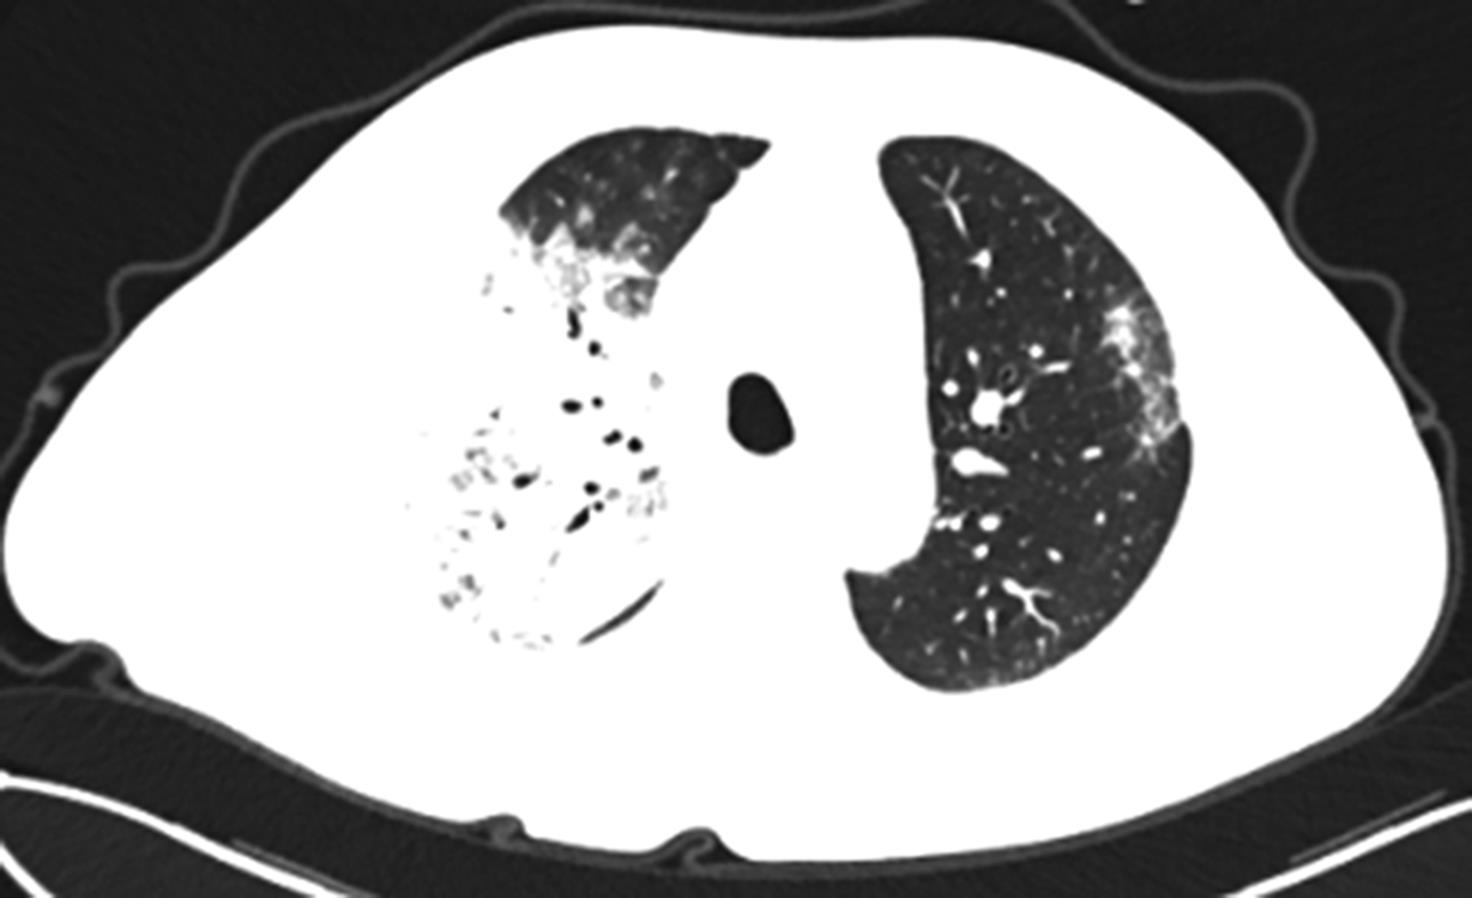

• 基于宏基因组二代测序诊断15例鹦鹉热衣原体肺炎临床特征与诊治分析

2023, 48(6):715-720. DOI: 10.13406/j.cnki.cyxb.003248

摘要 (49) HTML (29) PDF 858.28 K (202) 评论 (0) 收藏

摘要:目的 探讨和分析少见鹦鹉热衣原体肺炎的临床特征、诊治及预后,以期提升临床相关学科领域对该病的认识。方法 回顾性研究赣南医学院第一附属医院2017年1月至2022年12月确诊的15例鹦鹉热衣原体肺炎患者的临床资料,总结并分析该病的临床特征、诊断与鉴别要点,同时检索国内外文献资料对鹦鹉热衣原体肺炎的最新诊疗进展予以系统性讨论。结果 纳入本研究的15例鹦鹉热衣原体肺炎患者中,男性10例(66.67%),女性5例(33.33%),年龄62(32~79)岁,禽类接触史14例(93.33%),基础疾病史8例(53.3%),转化为重症肺炎5例(33.33%)。15例患者中,白细胞计数(white blood cell count,WBC)正常8例(53.3%),WBC升高5例(33.3%),WBC减低2例(13.3%);血红蛋白(hemoglobin,HGB)正常9例(60.0%),减低6例(40.0%);中性粒细胞百分比(neutrophils,NE)升高13例(86.7%);所有患者(100.0%)C反应蛋白(C-reactive protein,CRP)均显著升高;13例(86.67%)患者降钙素原(procalcitonin,PCT)升高;12例(80.0%)患者乳酸脱氢酶(lactate dehydrogenase,LDH)升高;11例(73.33%)肝功能异常;8例(53.33%)肾功能异常;6例(40.0%)凝血功能异常;13例(86.7%)电解质紊乱。此外,11例(73.33%)患者动脉血气分析显示不同程度血氧分压降低,8例(53.33%)氧合指数(oxygenation index,OI)低于300 mmHg,4例(26.67%)患者无明显呼吸困难,未进行动脉血气分析检查。本研究所有患者均已完善经支气管镜检查,并获取支气管肺泡灌洗液(bronchoalverolar lavage fluid,BALF)行宏基因组二代测序(metagenomic next-generation sequencing,mNGS)检测,检出的病原体除鹦鹉热衣原体外,所有患者均合并多种病原体感染。15例患者均已完善肺部电子计算机断层扫描(computed tomography,CT)等影像学检查,单侧肺部实变7例(46.67%),双侧实变8例(53.33%);9例(60.0%)患者伴有胸腔积液,部分患者可以表现出多种影像学表现,包括实变影、磨玻璃影、团块样实变影、反晕征、纵隔和肺门淋巴结肿大等。15例鹦鹉热衣原体肺炎患者在确诊后均予规范抗感染治疗,其中5例重症肺炎患者中2例患者予体外膜肺氧合(extracorporeal membrane oxygenation,ECMO)辅助治疗,所有患者均未见治疗相关不良反应或不良事件,平均住院日为13.9 d。本研究所有患者未见死亡,均好转出院。结论 鹦鹉热衣原体肺炎临床特征及表现缺乏特异性,易出现重症化,经支气管肺泡灌洗液予mNGS检测可精准确诊,早期予四环素类及喹诺酮类抗生素可最大程度改善患者预后。